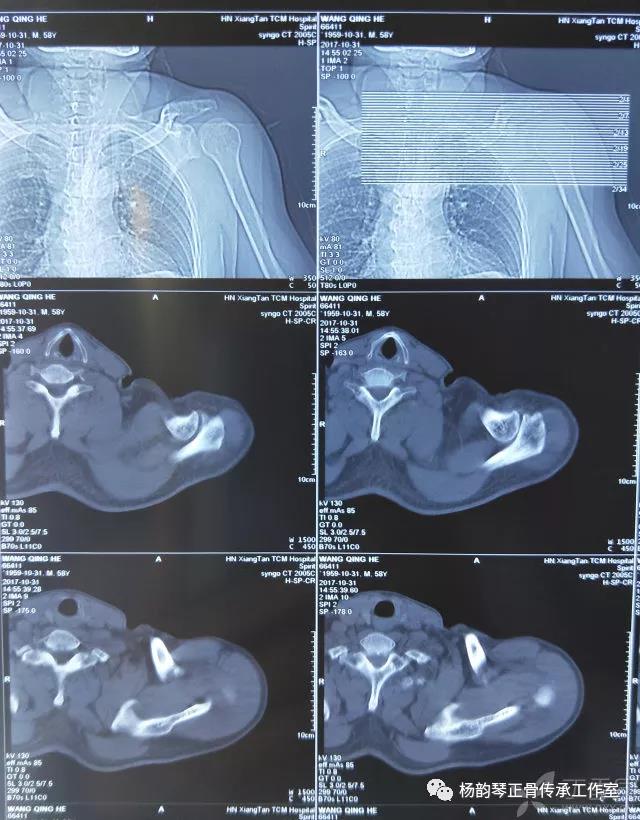

就诊我院后完善CT,诊断明确——左肩关节后脱位: